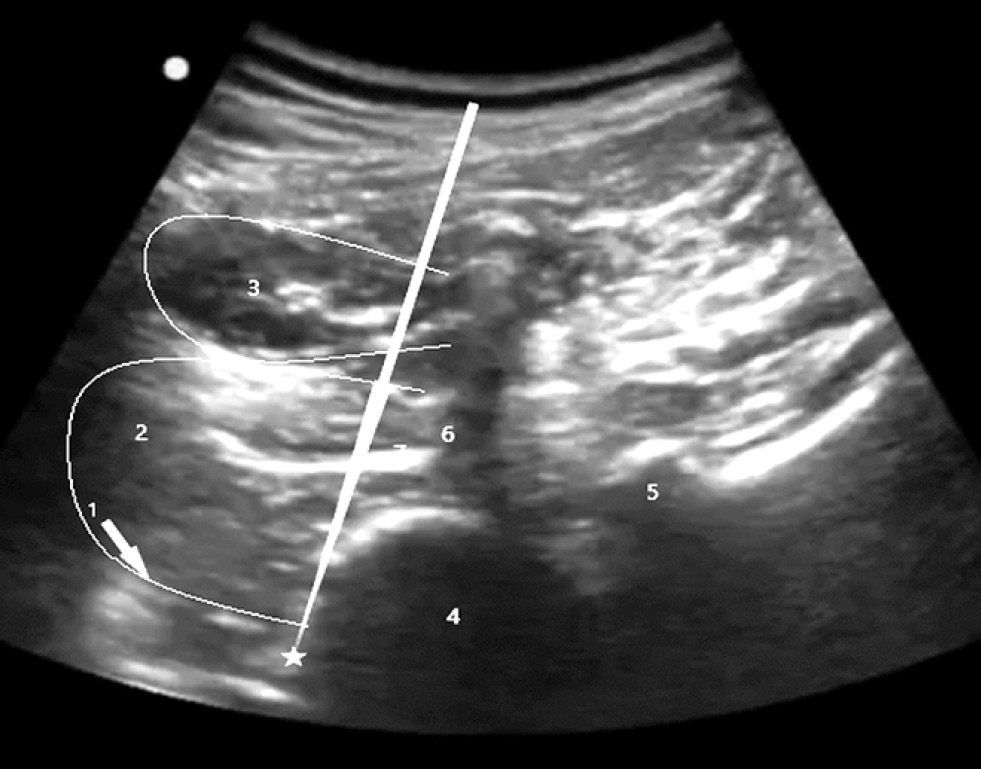

Оригинальный подход к блокаде поясничного симпатического ганглия под ультразвуковым контролем был предложен в 2017 г. По мнению авторов, прямая визуализация положения кончика иглы под передней фасцией большой поясничной мышцы в паравертебральном пространстве под контролем УЗИ должна иметь такие же показатели успеха, как и под контролем флюороскопа (рис. 5). Наряду с сокращением времени процедуры и уменьшением связанного с процедурой дискомфорта, который обычно может быть вызван касанием кончика иглы костного кортикального слоя позвонка при флюороскопическом контроле. Кроме того, ультразвуковой контроль также позволяет избежать повреждения внутренних органов [54]. Эффекты симпатических блокад не предсказывают успех стимуляции спинного мозга [55].

Рис. 5. Ультразвукассистированная блокада поясничного симпатического ганглия: 1 – передняя фасция поясничной мышцы; 2 – поясничная мышца; 3 – квадратная мышца поясницы; 4 – тень тела IV поясничного позвонка; 5 – суставной отросток позвонка; 6 – тень от поперечного отростка позвонка; 7 – поясничное сплетение / Fig. 5. Ultrasound-assisted blockade of the lumbar sympathetic ganglion: 1 – anterior fascia of the psoas muscle; 2 – psoas muscle; 3 – square muscle of the lower back; 4 – shadow of the body of the IV lumbar vertebra; 5 – articular process of the vertebra; 6 – shadow from the transverse process of the vertebra; 7 – lumbar plexus